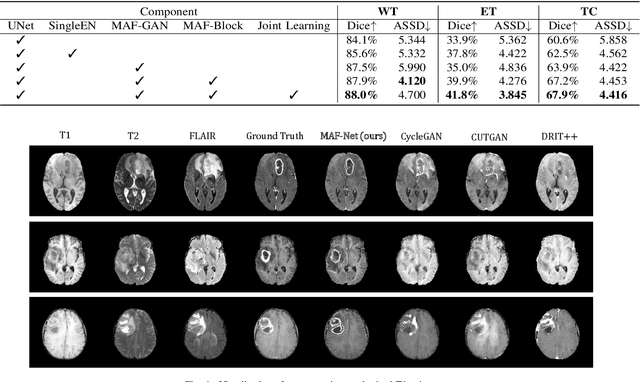

Abstract:Multi-modal magnetic resonance (MR) imaging provides great potential for diagnosing and analyzing brain gliomas. In clinical scenarios, common MR sequences such as T1, T2 and FLAIR can be obtained simultaneously in a single scanning process. However, acquiring contrast enhanced modalities such as T1ce requires additional time, cost, and injection of contrast agent. As such, it is clinically meaningful to develop a method to synthesize unavailable modalities which can also be used as additional inputs to downstream tasks (e.g., brain tumor segmentation) for performance enhancing. In this work, we propose an end-to-end framework named Modality-Level Attention Fusion Network (MAF-Net), wherein we innovatively conduct patchwise contrastive learning for extracting multi-modal latent features and dynamically assigning attention weights to fuse different modalities. Through extensive experiments on BraTS2020, our proposed MAF-Net is found to yield superior T1ce synthesis performance (SSIM of 0.8879 and PSNR of 22.78) and accurate brain tumor segmentation (mean Dice scores of 67.9%, 41.8% and 88.0% on segmenting the tumor core, enhancing tumor and whole tumor).